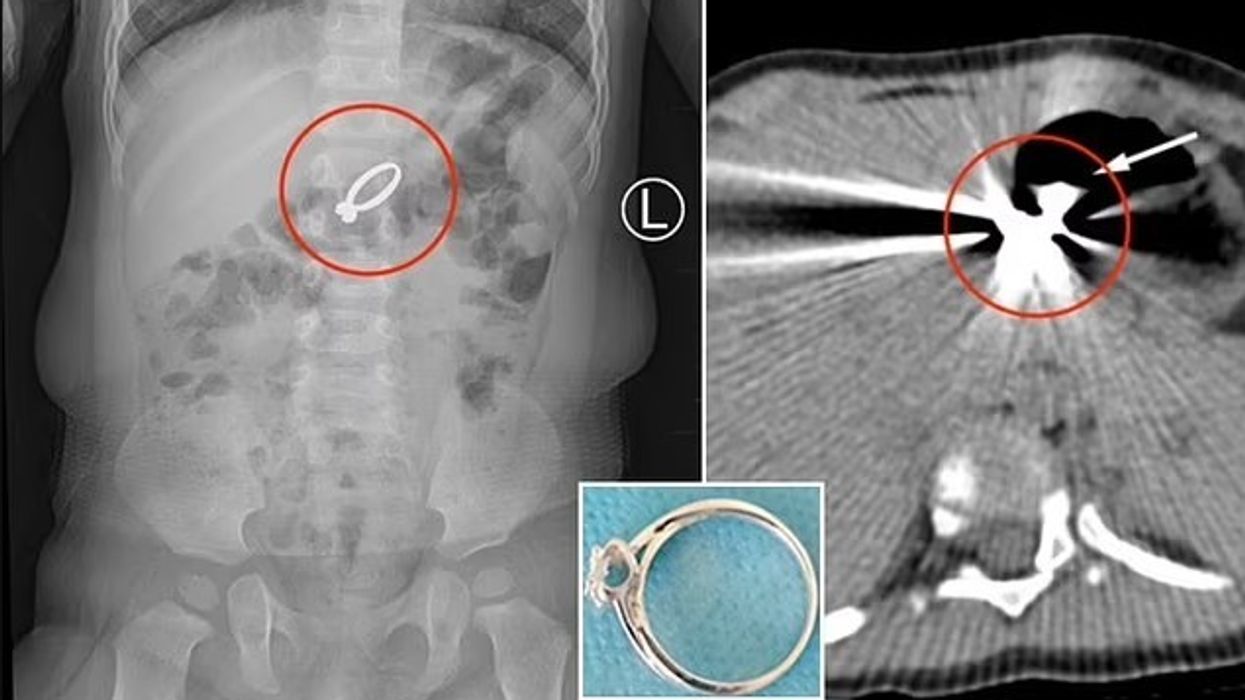

Kjo grua e dërgoi me urgjencë në spital të bijën 15-muajshe në Qingdao të Kinës, ku pas kryerjes së rëntgenografisë është zbuluar lokacioni i unazës së ëmës dhe arsyet pse vajza e saj kishte ankesa.

Unaza kishte përfunduar në barkun e vogëlushes, dhe për t’ia larguar mjekët u detyruan të kryejnë një ndërhyrje kirurgjike.